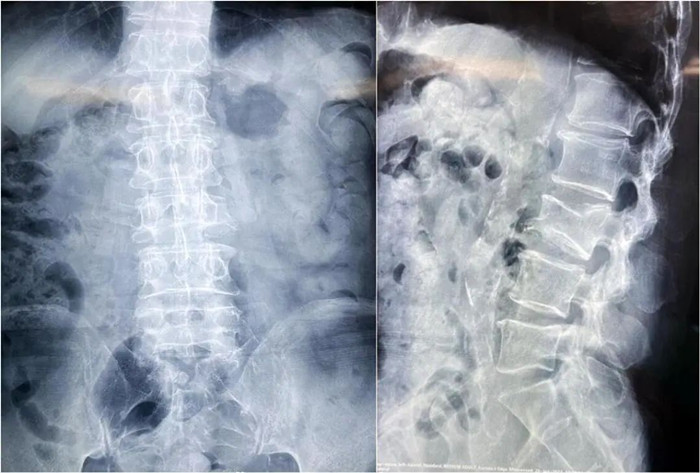

患者情況:腰椎L3壓縮性骨折

南京醫(yī)科大學(xué)第二附屬醫(yī)院骨科副主任醫(yī)師王伯堯帶領(lǐng)團(tuán)隊(duì)成功完成經(jīng)皮椎體球囊擴(kuò)張成形術(shù)(PKP)。該患者為腰椎陳舊性壓縮性骨折,腰部疼痛難忍,活動受限,生活受到影響。王醫(yī)生借助普愛醫(yī)療大平板C臂機(jī)高清的圖像及靈活的擺位,快速定位椎弓根位置,確定進(jìn)針點(diǎn),使得手術(shù)得以更加高效和準(zhǔn)確地完成。

患者術(shù)前影像